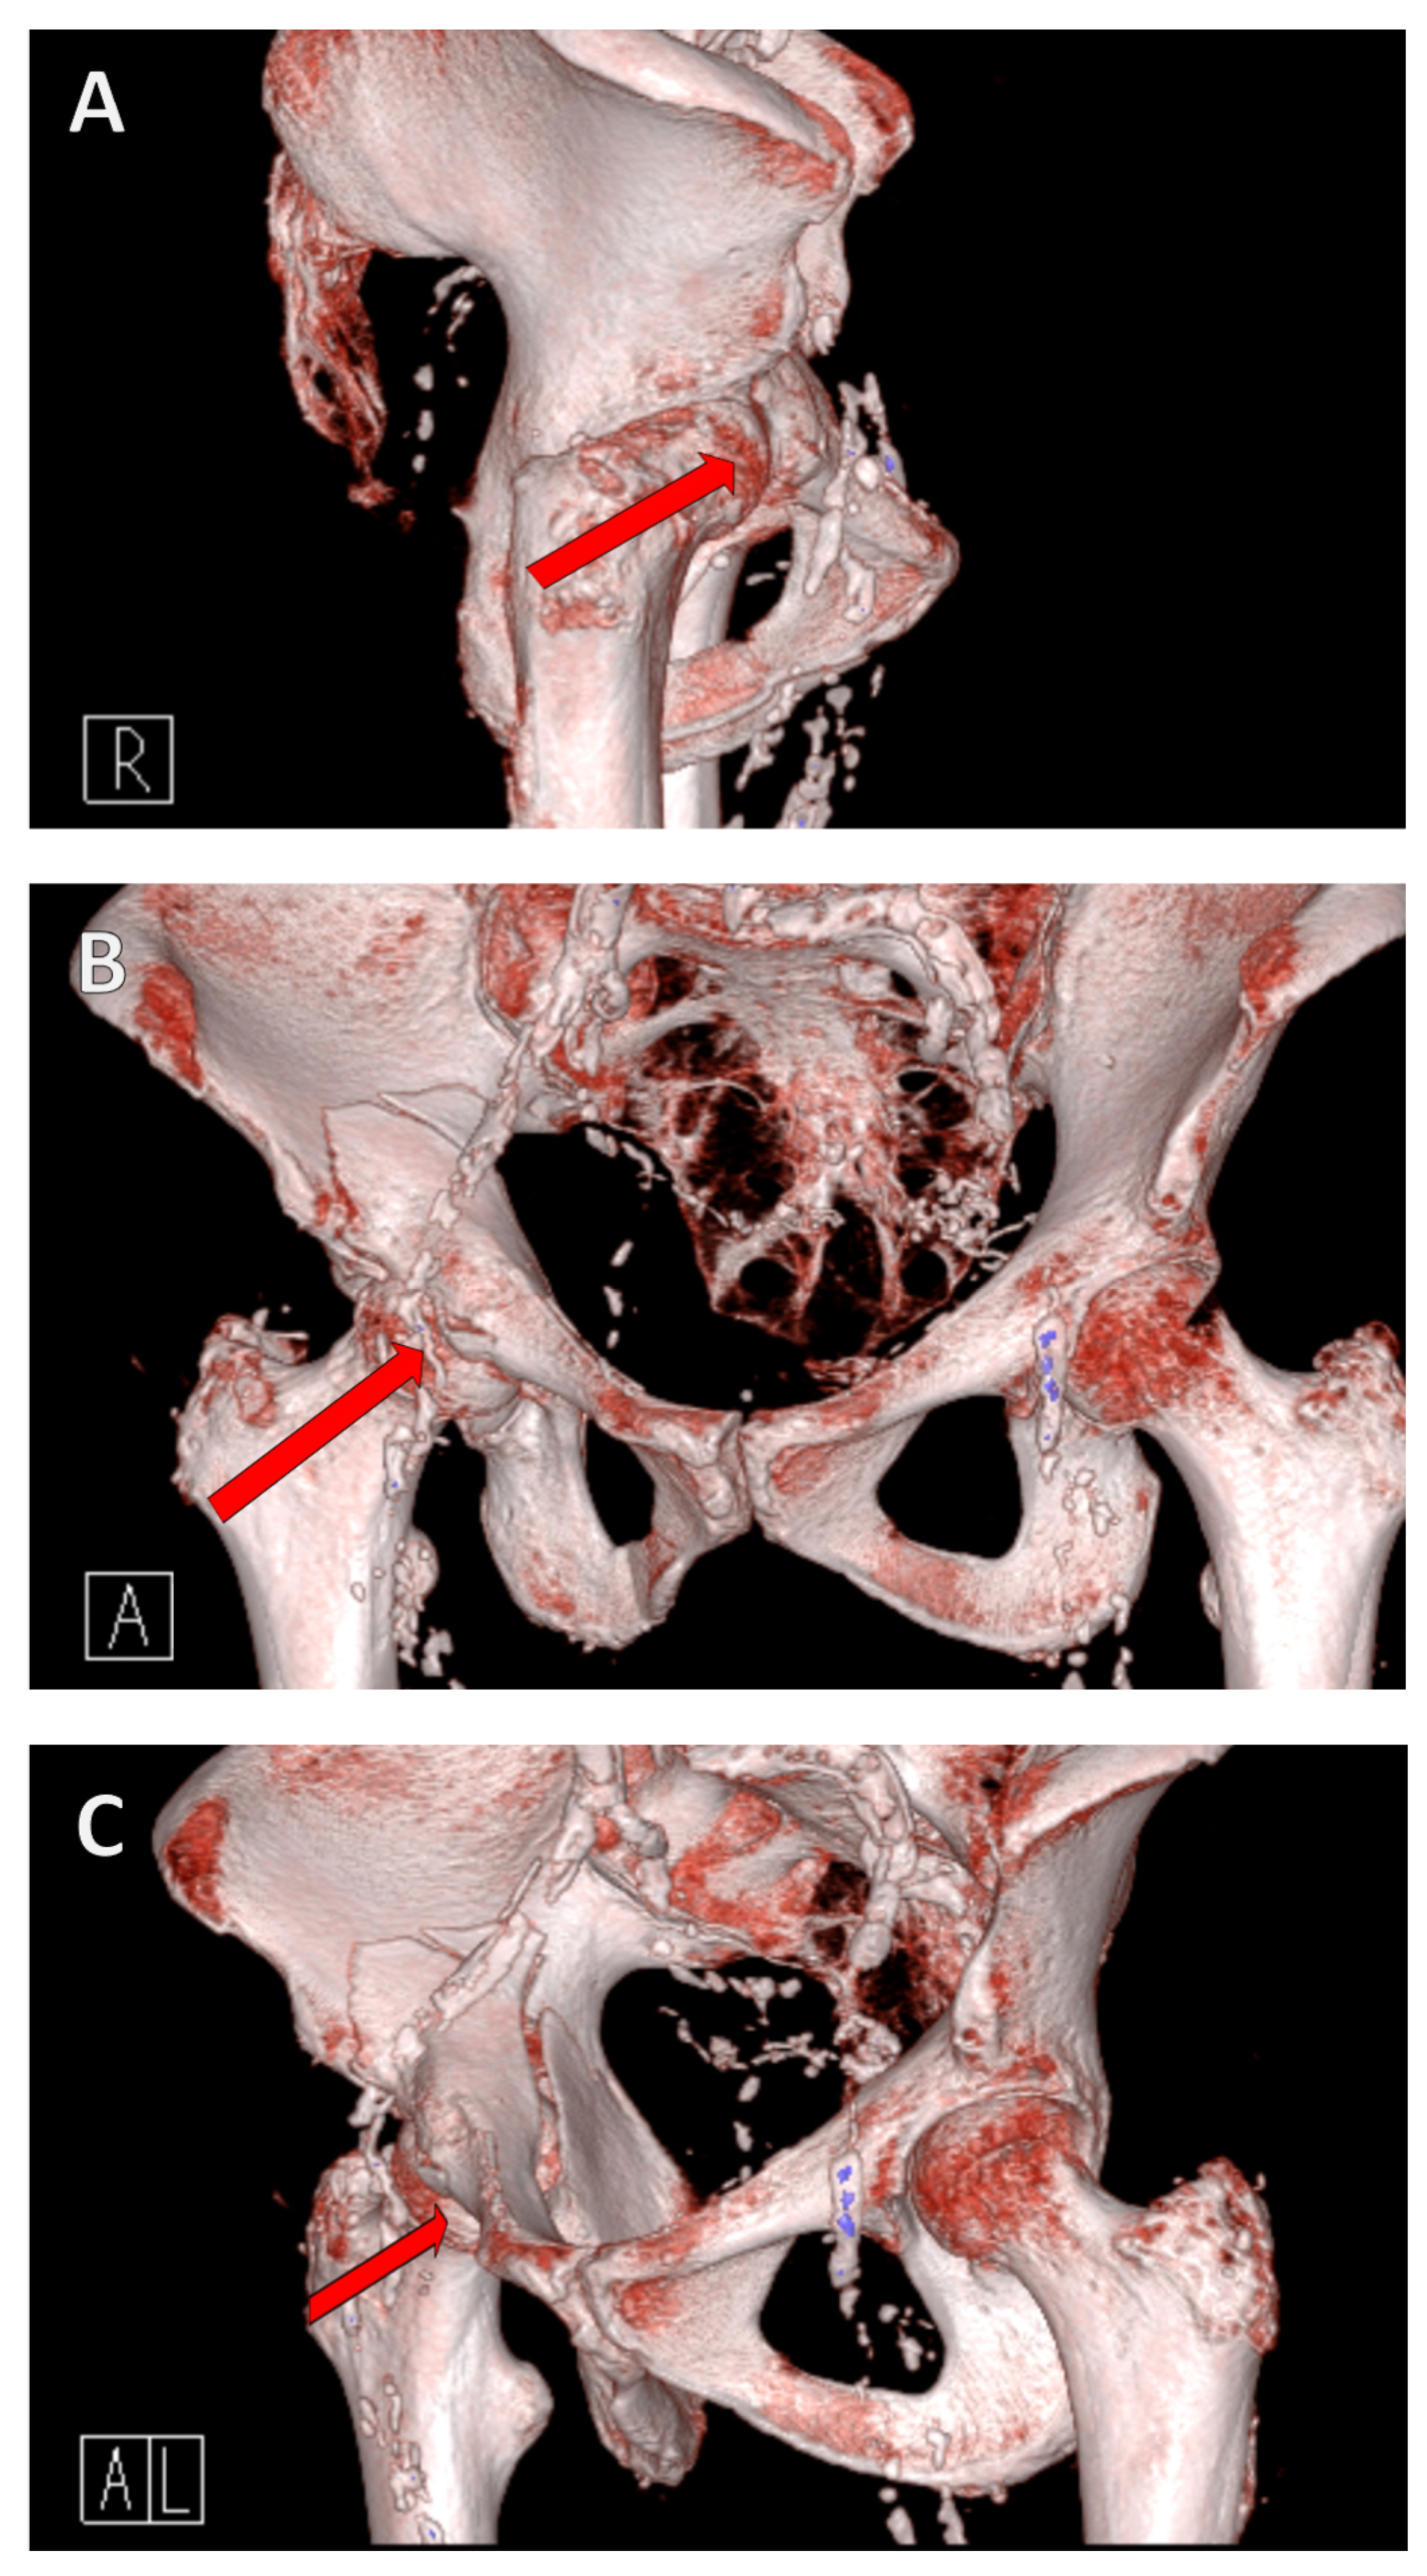

The mechanism of the fracture is as follows: a fall from a standing position causes a lateral fall onto the hip. This results in a transfer of force from the greater trochanter via the femoral neck to the femoral head, where the force is then transmitted to the anterior superior in the acetabulum itself due to the femoral anatomy (Figure 1).

Figure 1. Fracture mechanism of a geriatric acetabular fracture. A fall from a standing position to the side results in a transfer of force from the greater trochanter via the femoral neck to the femoral head, where the force is then transferred to the anterior superior into the acetabulum. A reduced bone density causes the acetabulum to collapse/fracture. The red arrow in the illustration shows the force trajectory, from the right lateral (A), anterior (B), and left anterolateral views (C).